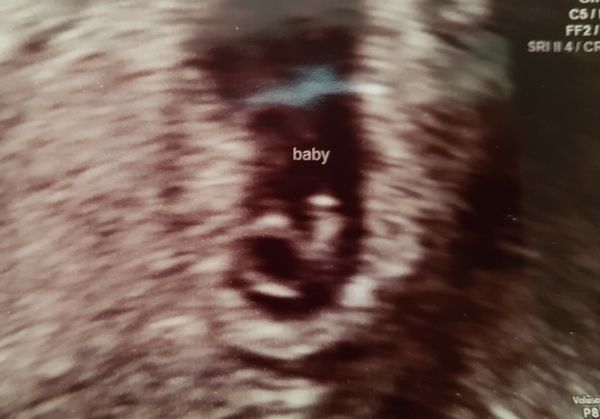

So after a real scare at the weekend I ended up in A+E and was referred for an emergency scan this morning.

Happy to say my little Squidge is all happy and snug, heart beating away nice and strong and measuring near enough bang on at 6+1. I'm so in love!

@clairehr. I'm 6w 1d too:-) I had a scan today. I thought I was 6w 6d but she said it all looked good and there was a heartbeat. How long was your bean in mm?

@Lookingatthestars89 Isn't it incredible?! I thought I was 6+2, so pretty much spot on. CRL is 4.6mm.

@clairehr. I thought I was going to be sick when she first turned the screen on as I couldn't see anything lol. My crl was 5.46mm which seems bigger than most people 6 weeks!

@LookingattheStars89 It does seem bigger than most I've heard of, think it all depends on how baby is lying etc. I don't think they depend on it at this stage, not until the 12 week scan where they will date 'properly' 😊

Lovely seeing the scan pictures! Xx